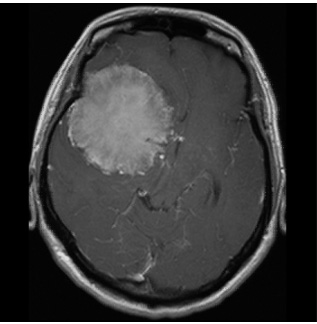

図2 頭蓋底髄膜腫 48歳女性 歩行障害、嚥下困難で来院

術後MRI:海綿静脈洞への浸潤部を除き

摘出、歩行障害改善し退院